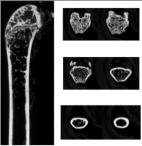

| 非常重要的观察部位,最好附参考图或文献链接 | ![]() | |||